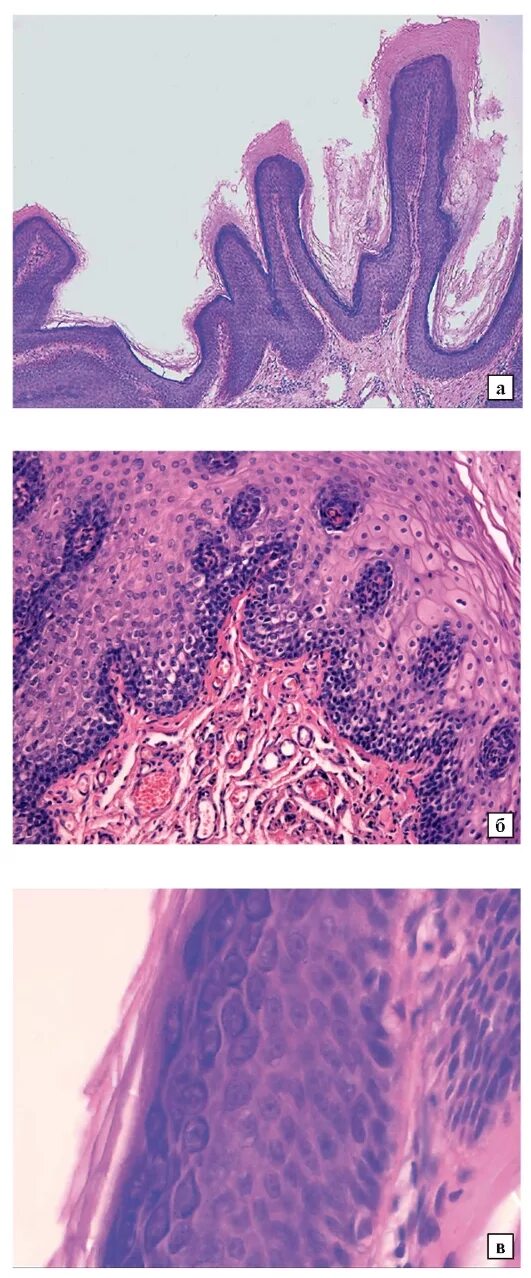

Папиллома гистология